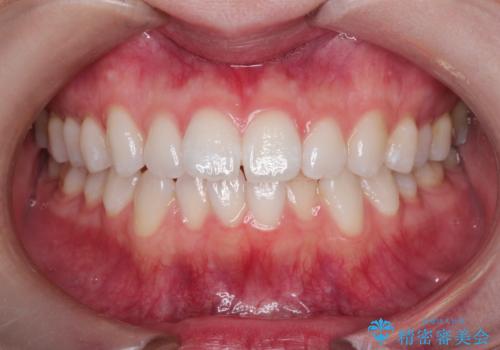

- 上下の前歯の凸凹が気になり、来院されました。

インビザラインで綺麗に仕上がり、満足していただきました。